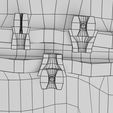

神经肌肉接头示意图

| 设计者 | deepuparmar |